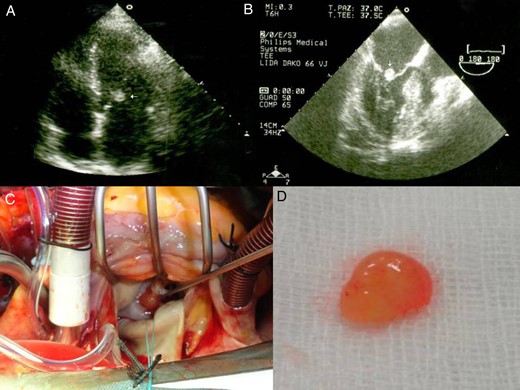

A 52-year-old woman was readmitted to a regional hospital due to wound infection after a previous mastectomy due to breast cancer. She received antibiotics for 2 weeks to treat a suspicious vegetation apparent on transthoracic echocardiography (Fig. 1A). Because the size of the cardiac mass had not changed, the patient was referred to our hospital for further evaluation.

Transthoracic echocardiography shows a mobile and spherical mass of 1.0 cm in size attached to anterior mitral leaflet. Parasternal long-axis view (A) and an apical four-chamber view (B). Gross specimen of excised mass reveals a friable mass with frond-like surface.

On physical examination, her blood pressure, pulse and respiration rates were within normal values. The body temperature was 37.5°C. The laboratory findings revealed 15 700/mm3 leucytosis, platelet count 3 251 000/mm3 and erythrocyte sedimentation rate 53 mm/h. Results of urinalysis, blood chemistry and electrolyte tests were within normal ranges. TEE revealed a mass of >1.0 cm in size, mobile, attached to anterior mitral leaflet on the atrial aspect, and round with a homogenously speckled surface (Fig. 1B). There was moderate to severe mitral regurgitation.

The cardiac mass was removed by surgery in order to reduce the risk of embolism as well as to rule out the infective endocarditis. Under standard cardiopulmonary bypass, the left atrium was opened and the mass was identified (Fig. 1C). The mass was removed using a shave excision technique. However, there was significant mitral regurgitation after mass excision, and following excision of the mitral leaflets and chordae, a mechanical valve was implanted with preservation of the subvalvular apparatus of the mitral valve.

Macroscopically, the excised lesion was composed of a soft beige tissue with micropapillary projections and lobulated surface of 1.2 × 0.5 cm, entirely processed (Fig. 1D). The mass appeared yellowish, with polypoid and fibrotic characteristics. After the surgical excision, the mass was fixed in formalin, paraffin embedded, sectioned at 3 μm thick and stained conventionally with hematoxylin and eosin. The histology examination revealed a papillary lesion composed of numerous papillary fronds with an acellular fibro-hialinous stroma (Fig. 2A and B). Those projections are covered by endothelial cells (Fig. 2C). In the excised margin in close contact with the non-pathologic endocardial tissue, the lesion has an infiltrative-like appearance, but the excisional margin itself was free of neoplasia. A higher magnification demonstrates a myxoid papillary structure lined by endothelial cells that express endothelial cell markers (Fig. 2D). The diagnosis of PFE was confirmed. The postoperative course was uneventful, and the patient was discharged in a satisfactory condition on the seventh day.